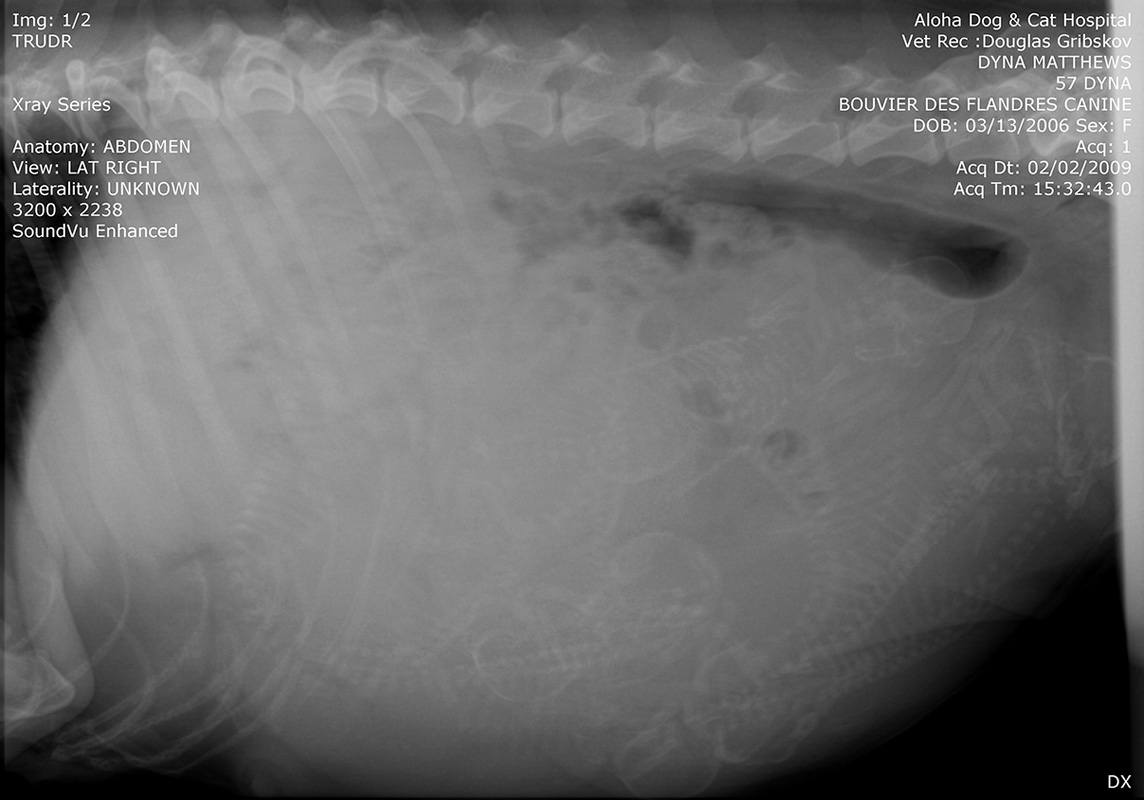

Default X-Ray of Dyna's Puppies

Here is one of the x-rays taken of Dyna showing that she does indeed have a belly full of little Bouviers... or as Sue says, "The Eight is Enough Echo Bouvier Litter". What Mike says we won't get into.